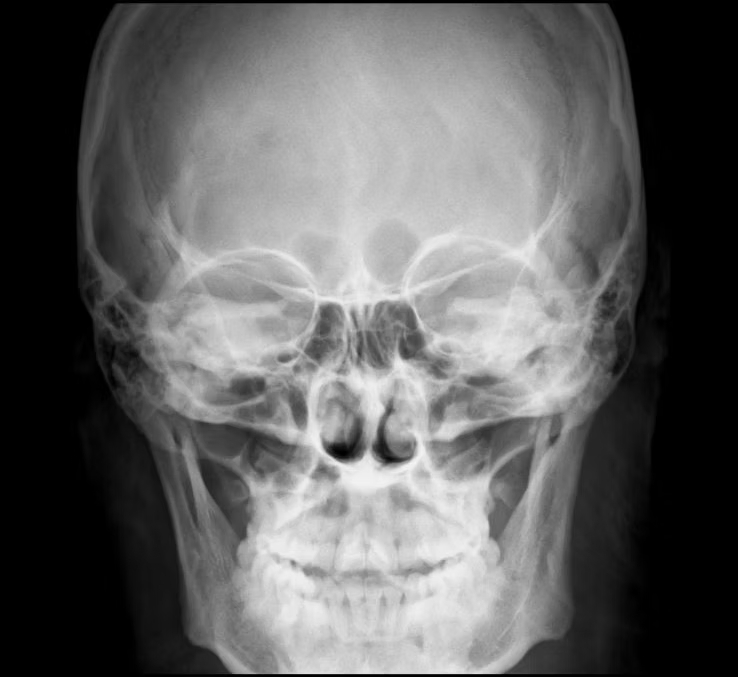

Télécrâne

La téléradiographie du crâne (télécrâne) est un examen radiographique permettant l’analyse des structures osseuses cranio-faciales à des fins orthodontiques.